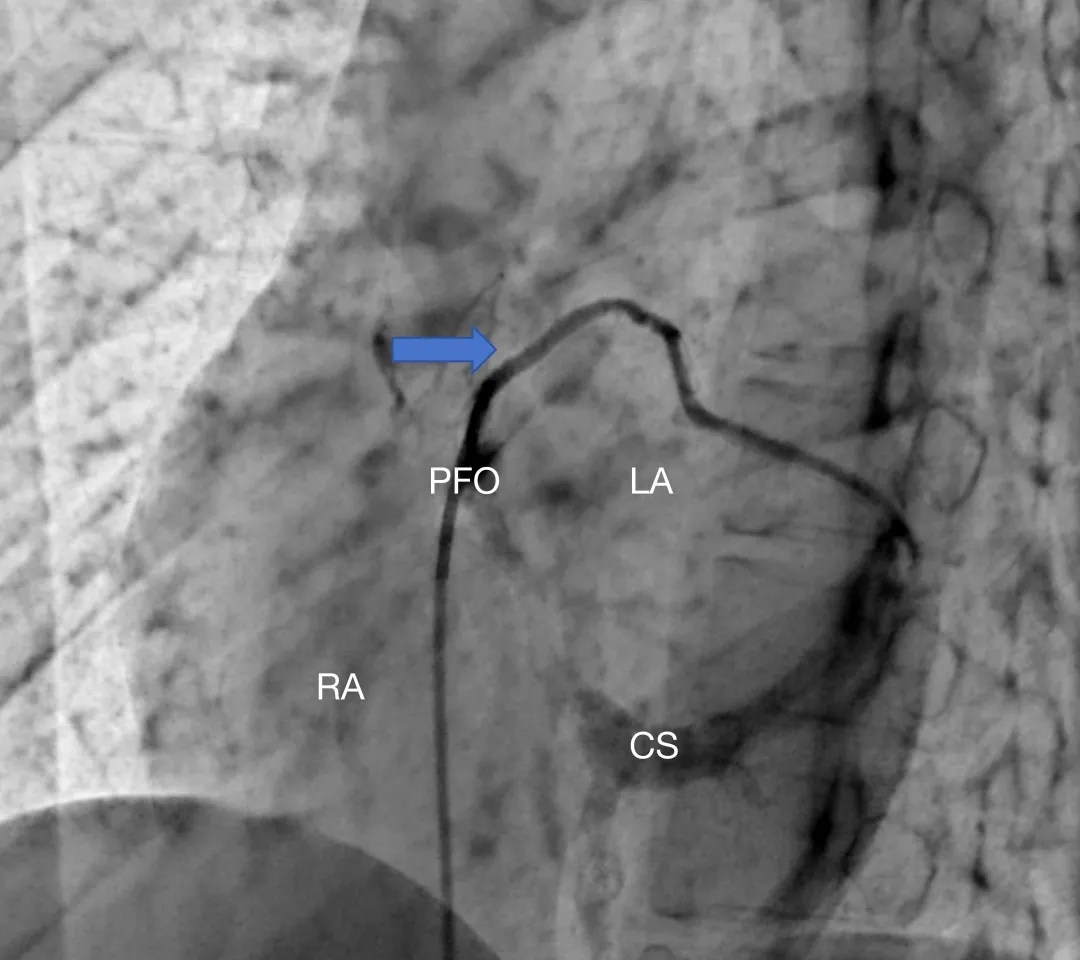

患者女性,27岁,因“卵圆孔未闭相关卒中”入院,拟行介入封堵术。术中MPA1导管跨越卵圆孔进入左心房后送入超滑导丝,发现导丝经由冠状静脉窦走行区回到右心房内,考虑导管进入异常通道,进一步造影可见一起自左心房前壁的冠状静脉分支血管沿房间隔水平横行走行,造影剂最终汇入冠状静脉窦,引流入右心房(图1&2,视频1&2)。该病情血液动力学类似冠状静脉无顶综合征/房间隔缺损,同期行右心导管测肺动脉平均压16mmHg,QP/QS=1.0,排除具有血液动力学意义的左向右分流。由于无法立刻明确单纯封堵PFO的收益与风险,遂终止手术先行完成心脏增强CT明确病变解剖情况,增强CT(图3&4)及重建结果(图5&6)与造影一致,可见一冠状静脉分支起自左心房并沿房间隔走行最终汇入冠状静脉窦。考虑到患者的临床症状可能与PFO以及该异常静脉均存在相关性,且尚不能明确单纯封堵PFO的收益以及同期封堵该静脉的风险,与患者充分沟通后暂时选择最优药物治疗并保持密切随访。

图2